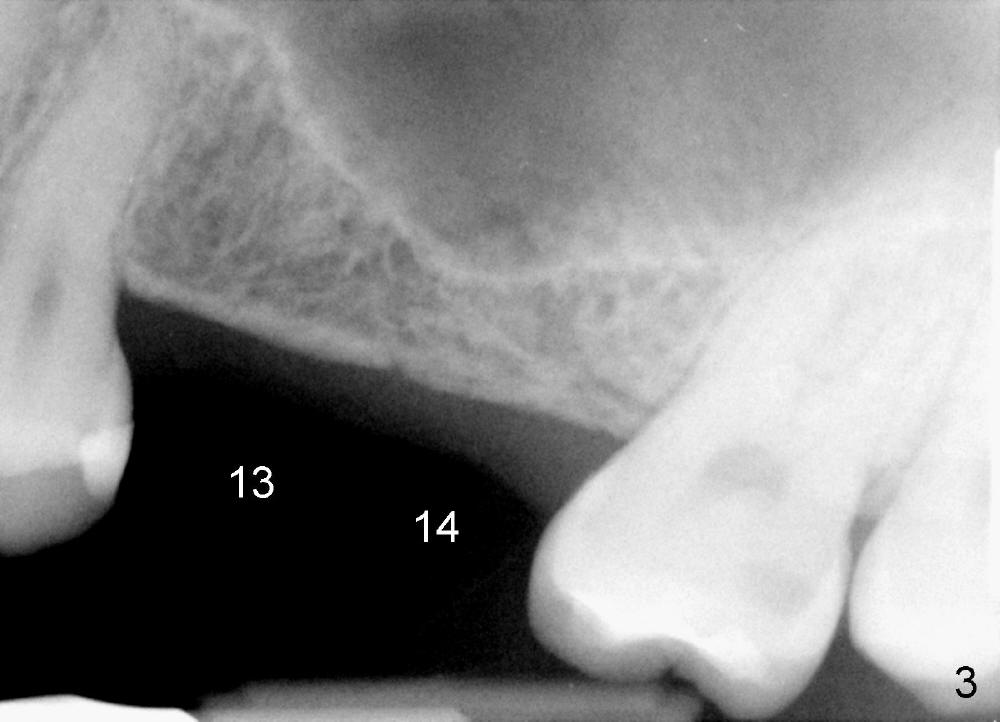

Bone height is limited for implant placement at the sites of the 2nd premolar and the 1st molar (Fig.3: #13,14), 7.68 and 4.45 mm, respectively (Fig.4).  The depth of the pilot drills is controlled between 6 and 8 mm for #13 and less than 6 mm for #14 at the crest.